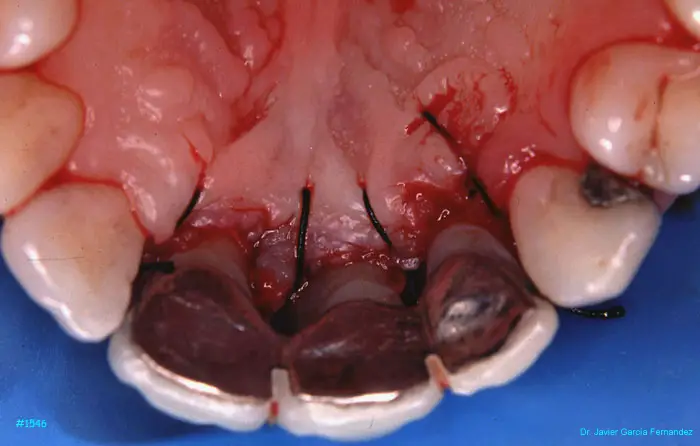

Atlas of Surgical Techniques in Periodontics. Chapter IV. Atlas de Técnicas Quirúrgica en Periodoncia

image 073